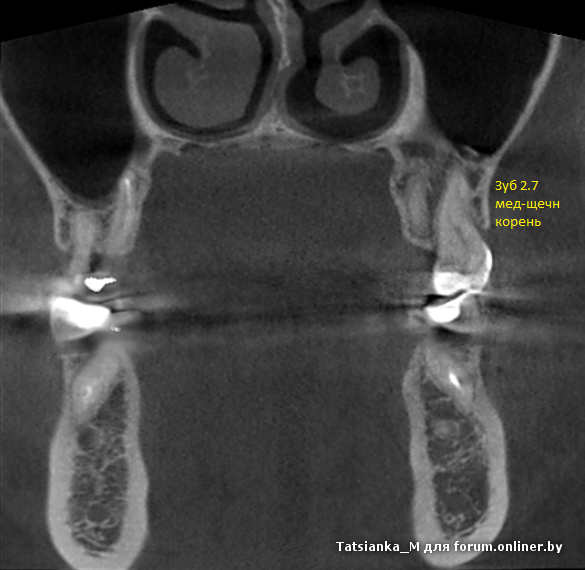

Ну вот я ни разу не врач, открываю сейчас первоначальное КТ и смотрю (да, я конечно уже знаю как, что и где примерно искать, но я не училась на стоматолога и не понимаю, почему я как пациент вообще должна что-то выискивать, показывать и доказывать, мое дело сделать снимок и явиться к врачу на лечение - и фффсё).

Аксиальный (Z): срезы на разных уровнях.

Формы мед-щечн корней (6ка и 7ка) - тонкие, сплюснутые по ширине, по два канала в каждом.

Коронарный (Y):

В шестерке легче, т.к. у каждого канала свой отдельный вход, оба канала относительно прямые и идут параллельно друг другу до апекса. При последующей перепломбировке зуба нашли, обработали, закрыли.

В семерке сложнее, т.к. один вход и на определенной глубине идет разветвление, действительно отчетливо видна петля.